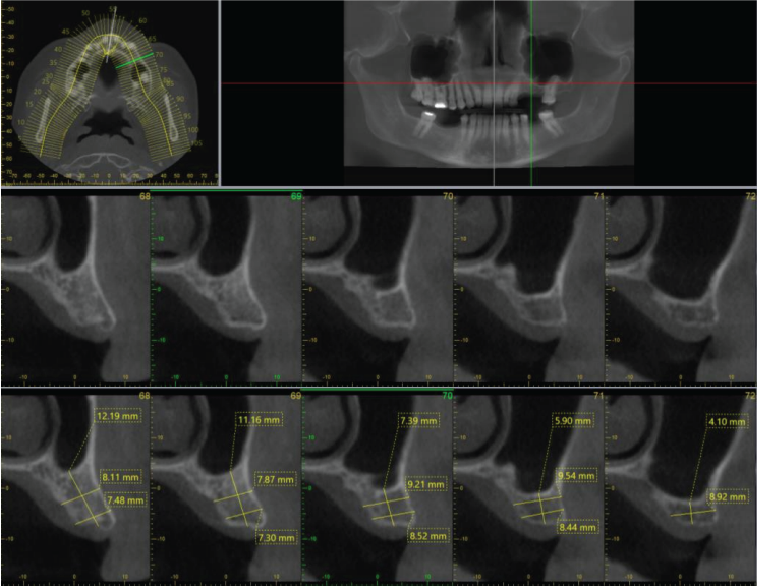

Periodontal bone levels are mainly normal or show mild bone loss, but there is greater bone loss associated with UR8 and UR7 and incidental finding of caries. UL4, UL5, UL6 sites have a mature alveolar ridge. No retained roots or bony pathosis. Selected images 3 are bucco-palatal cross-sections across the site. Bone height to the antral floor steadily falls moving distally across the site. There is a short transverse septum at the maxillary antral floor above the palatal side of UL5 site, which should not be relevant to any sinus lift procedure being planned. The alveolar bone quality appears satisfactory, with fairly dense trabeculation and well-defined cortices. The LL6 site has a mature alveolar ridge with no retained roots or bony pathothis. LL7 is mesially inclined, so that its crown overhangs the site. Selected images 4 are bucco-lingual cross-sections across the site. The alveolar ridge has a broad crest. There is a mild lingual undercut, with a lingual concavity present mesially in the site and in the premolar region. The lingual concavity of the submandibular fossa appears towards the distal end of the site. The ID canal is easily identified, lying quite low in the bone. The mental canal is in the plane of LL5. Bone quality is satisfactory, with well-defined thick cortices and fairly evenly trabeculated medullary bone.

Image 3

Image 4